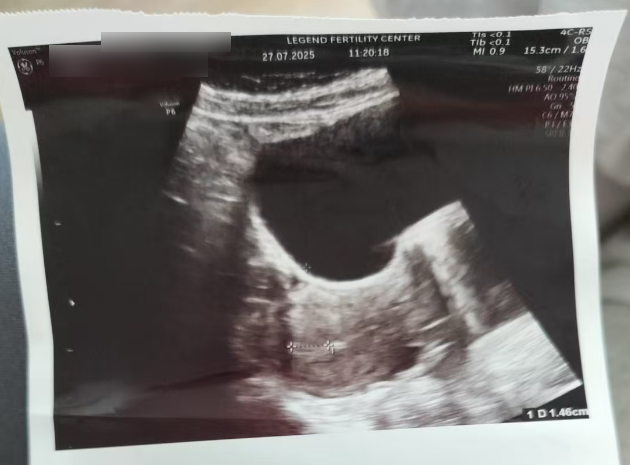

7月22日,H女士进行首次超声检查,结果显示孕酮>1.5ng/ml,且内膜呈现 “三线模糊” 状态。

这两个指标背后,藏着移植前的潜在风险:

• 孕酮>1.5ng/ml

- 酮过高可能提示卵巢黄体功能提前活跃,干扰内膜对胚胎的接受度

• 内膜三线模糊

- 试管移植中,理想内膜需清晰“三线征”,代表容受性好,适合胚胎着床,此时的内膜条件不利于胚胎着床。